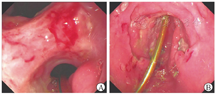

患者入院体格检查示体温为36.7 ℃,血压为110/75 mmHg(1 mmHg=0.133 kPa),脉率为85次/min,体重指数为14.3 kg/m2(身高为1.63 m,体重为38 kg),消瘦,慢性病容。双肺呼吸音较弱,腹韧,上腹部深压痛,无反跳痛、肌紧张。肝脾肋下未及,未及腹部包块。肠鸣音为2~3次/min。双下肢无水肿。血常规检查示白细胞计数为5.07×109/L,血红蛋白为108 g/L,血小板计数为309×109/L,粪便隐血试验阳性,肝、肾功能无异常,超敏C反应蛋白(hypersensitive C-reactive protein,hsCRP)为18.00 mg/L,红细胞沉降率为41 mm/1 h,铁蛋白为82 ng/mL,凝血功能无异常。结核菌素试验、结核感染特异性T细胞检测结果均呈阴性。外周血巨细胞病毒和EB病毒DNA、巨细胞病毒免疫球蛋白M、巨细胞病毒抗原血症检测结果均呈阴性。外周血需氧菌、厌氧菌、结核分枝杆菌、真菌培养和痰液病原学培养结果均呈阴性;胃黏膜活检组织结核分枝杆菌DNA检测(聚合酶链反应法)结果呈阴性。胸腔积液检验示白细胞计数为880×106/L,单核细胞占94.8%,ADA为60.2 U/L,结核感染特异性T细胞检测阳性[以每1×106个单个核细胞(mononuclear cell,MC)中斑点形成细胞(spot forming cell,SFC)的数目计,为64 SFC/(1×106MC)],细菌和真菌培养结果均呈阴性。抗核抗体谱、抗中性粒细胞胞质抗体、针刺试验结果均呈阴性。糖类抗原125为56.9 U/mL,胃泌素为127 pg/mL(未停用PPI),血清和尿免疫固定电泳检查均未见异常,在胸腔积液中未找到肿瘤细胞。腹盆部增强CT检查示胃体和胃底部黏膜面不规则伴黏膜面异常强化。2022年2月11日复查胃镜,于胃角见巨大溃疡,横贯胃角,延伸至幽门口,溃疡表面薄白苔,窦体交界前壁另可见2处长径为5~10 mm、与胃角溃疡外形特点相似的溃疡(图1);幽门螺杆菌快速尿素酶试验结果呈阴性;活检病理示胃黏膜中度慢性炎和轻度活动性炎,局部腺体增生,高倍视野下未见异常形态;免疫组织化学检查示巨细胞病毒阴性;特殊染色检查示抗酸染色未见抗酸杆菌,弱抗酸染色阴性;原位杂交技术检查示EB病毒编码的小RNA原位杂交(Epstein-Barr virus encoded small RNA-in situ hybridization,EBER-ISH)阴性。为除外淋巴瘤,2022年2月28日先后行超声内镜细针穿刺及胃镜下深挖和黏膜圈套活检,仍可见胃角、窦体交接前壁处巨大溃疡,溃疡形态、大小与2022年2月11日胃镜检查所见大致相同(图2);病理示(胃角)炎性渗出物和肉芽组织;免疫组织化学检查示CD10(部分阳性),Bcl-6阳性,CD2(T细胞)、CD3(T细胞)、CD20(B细胞)、CD4(T细胞)、CD5(T细胞)、CD7(T细胞)、CD8(T细胞)均阳性,Mum-1阳性,CD30(Ki-1)、CD56、巨细胞病毒均阴性,Ki-67指数为70%; EBER-ISH阴性。完善18F-氟代脱氧葡萄糖、正电子发射计算机断层显像检查见甲状腺左叶2个代谢增高的低密度结节,最大标准摄取值(maximum standard uptake value,SUVmax)为25.6;胃体大、小弯侧局部胃壁略增厚伴代谢增高(SUVmax为7.3);胃小弯侧、腹膜后多发代谢轻度增高淋巴结;右肺上叶代谢增高微结节,右肺中叶代谢增高结节、实变影(SUVmax为9.4)。甲状腺左叶代谢增高结节经超声穿刺活检确诊为甲状腺乳头状癌。